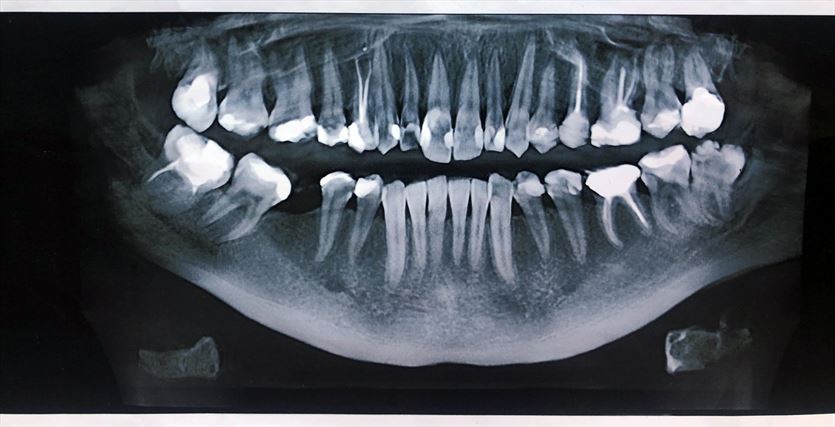

Rentgenodiagnostyka stomatologiczna odgrywa kluczową rolę w precyzyjnej ocenie stanu zdrowia zębów, kości szczęki, żuchwy oraz zatok szczękowych. Dzięki obrazowaniu radiologicznemu możemy wykryć zmiany niewidoczne gołym okiem, takie jak próchnica pod wypełnieniami, ubytki strukturalne, stany zapalne czy torbiele. Zdjęcia rentgenowskie są również niezbędne przy planowaniu leczenia ortodontycznego, implantologicznego oraz chirurgicznego.

W naszym gabinecie wykonujemy różne rodzaje zdjęć RTG, w tym:

• zdjęcia panoramiczne,

• zdjęcia punktowe,

• zdjęcia cefalometryczne.

Nasz sprzęt pozwala nam na uzyskanie obrazów o wysokiej rozdzielczości przy jednoczesnym minimalizowaniu dawki promieniowania. Zdjęcia wykonujemy zarówno w formie analogowej, drukowane na kliszy, jak i w wersji cyfrowej, zapisanej na płycie CD. Dzięki temu pacjenci mogą łatwo przechowywać i udostępniać wyniki badań lekarzom prowadzącym.